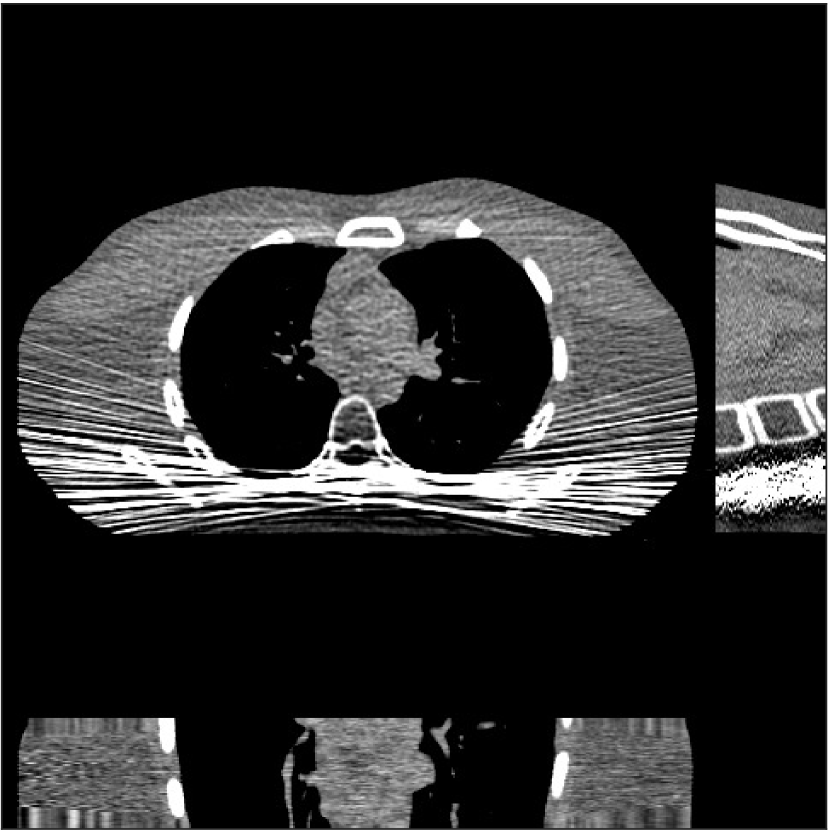

Fig. 4 shows the reconstructed images and the corresponding error images for PWLS-EP, PWLS-ULTRA, and SPULTRA, at and . Compared to the PWLS-EP result, both PWLS-ULTRA and SPULTRA achieved significant improvements in image quality in terms of sharper reconstructions of anatomical structures such as bones and soft tissues, and suppressing the noise. However, the PWLS-ULTRA method introduces bias in the reconstructions, which leads to larger reconstruction errors compared to the proposed SPULTRA method. In Fig. 4, we marked three 3D ROIs in the axial plane, i.e., ROI 1, ROI 2, and ROI 3. Fig. 5 shows the zoom-in images of a 3D plot of ROI 1, and those of ROI 2 and ROI 3 are shown in the supplement. We also plot the evolution of RMSE through the axial slices of the three 3D ROIs in Fig. 6. The figures demonstrate that SPULTRA clearly outperforms the competing PWLS-EP and PWLS-ULTRA schemes.

The above advantages of SPULTRA can be seen more clearly when observing the image profiles. Fig. 7 plots the image profiles for the three methods together with that of the ground-truth image. Fig. 4 shows the horizontal green solid line and the vertical red dashed line, whose intensities are plotted in Fig. 7. It is obvious that the profiles for SPULTRA are closest to the ground-truth among the three compared methods. The gap between the profiles of the PWLS-based methods and the ground-truth shows the bias caused by the compared PWLS methods.

Fig. 9 shows three axial slices from the 3D reconstructions with SPULTRA and PWLS-ULTRA at : the middle slice (No. 67) and two slices located farther away from the center (No. 90 and No. 120). The image profiles along a horizontal line (shown in green) in the displayed slices are also shown in Fig. 9. The reconstructed slices using PWLS-ULTRA appear darker around the center compared to the “true” clinical image and the reconstructions with SPULTRA. This means PWLS-ULTRA produces a strong bias in the reconstruction. The bias can be observed more clearly in the profile plots: the pixel intensities for the SPULTRA reconstruction better follow those of the “true” clinical image, while those for the PWLS-ULTRA reconstruction are much worse than the “true” values. Moreover, SPULTRA achieves sharper rising and failing edges compared to PWLS-ULTRA. In other words, SPULTRA also achieves better resolution than PWLS-ULTRA. Fig. 9 also shows a zoomed-in ROI for each of the chosen slices, and highlights some small details with arrows. It is clear that in addition to reducing the bias, SPULTRA reconstructs image details better than PWLS-ULTRA.